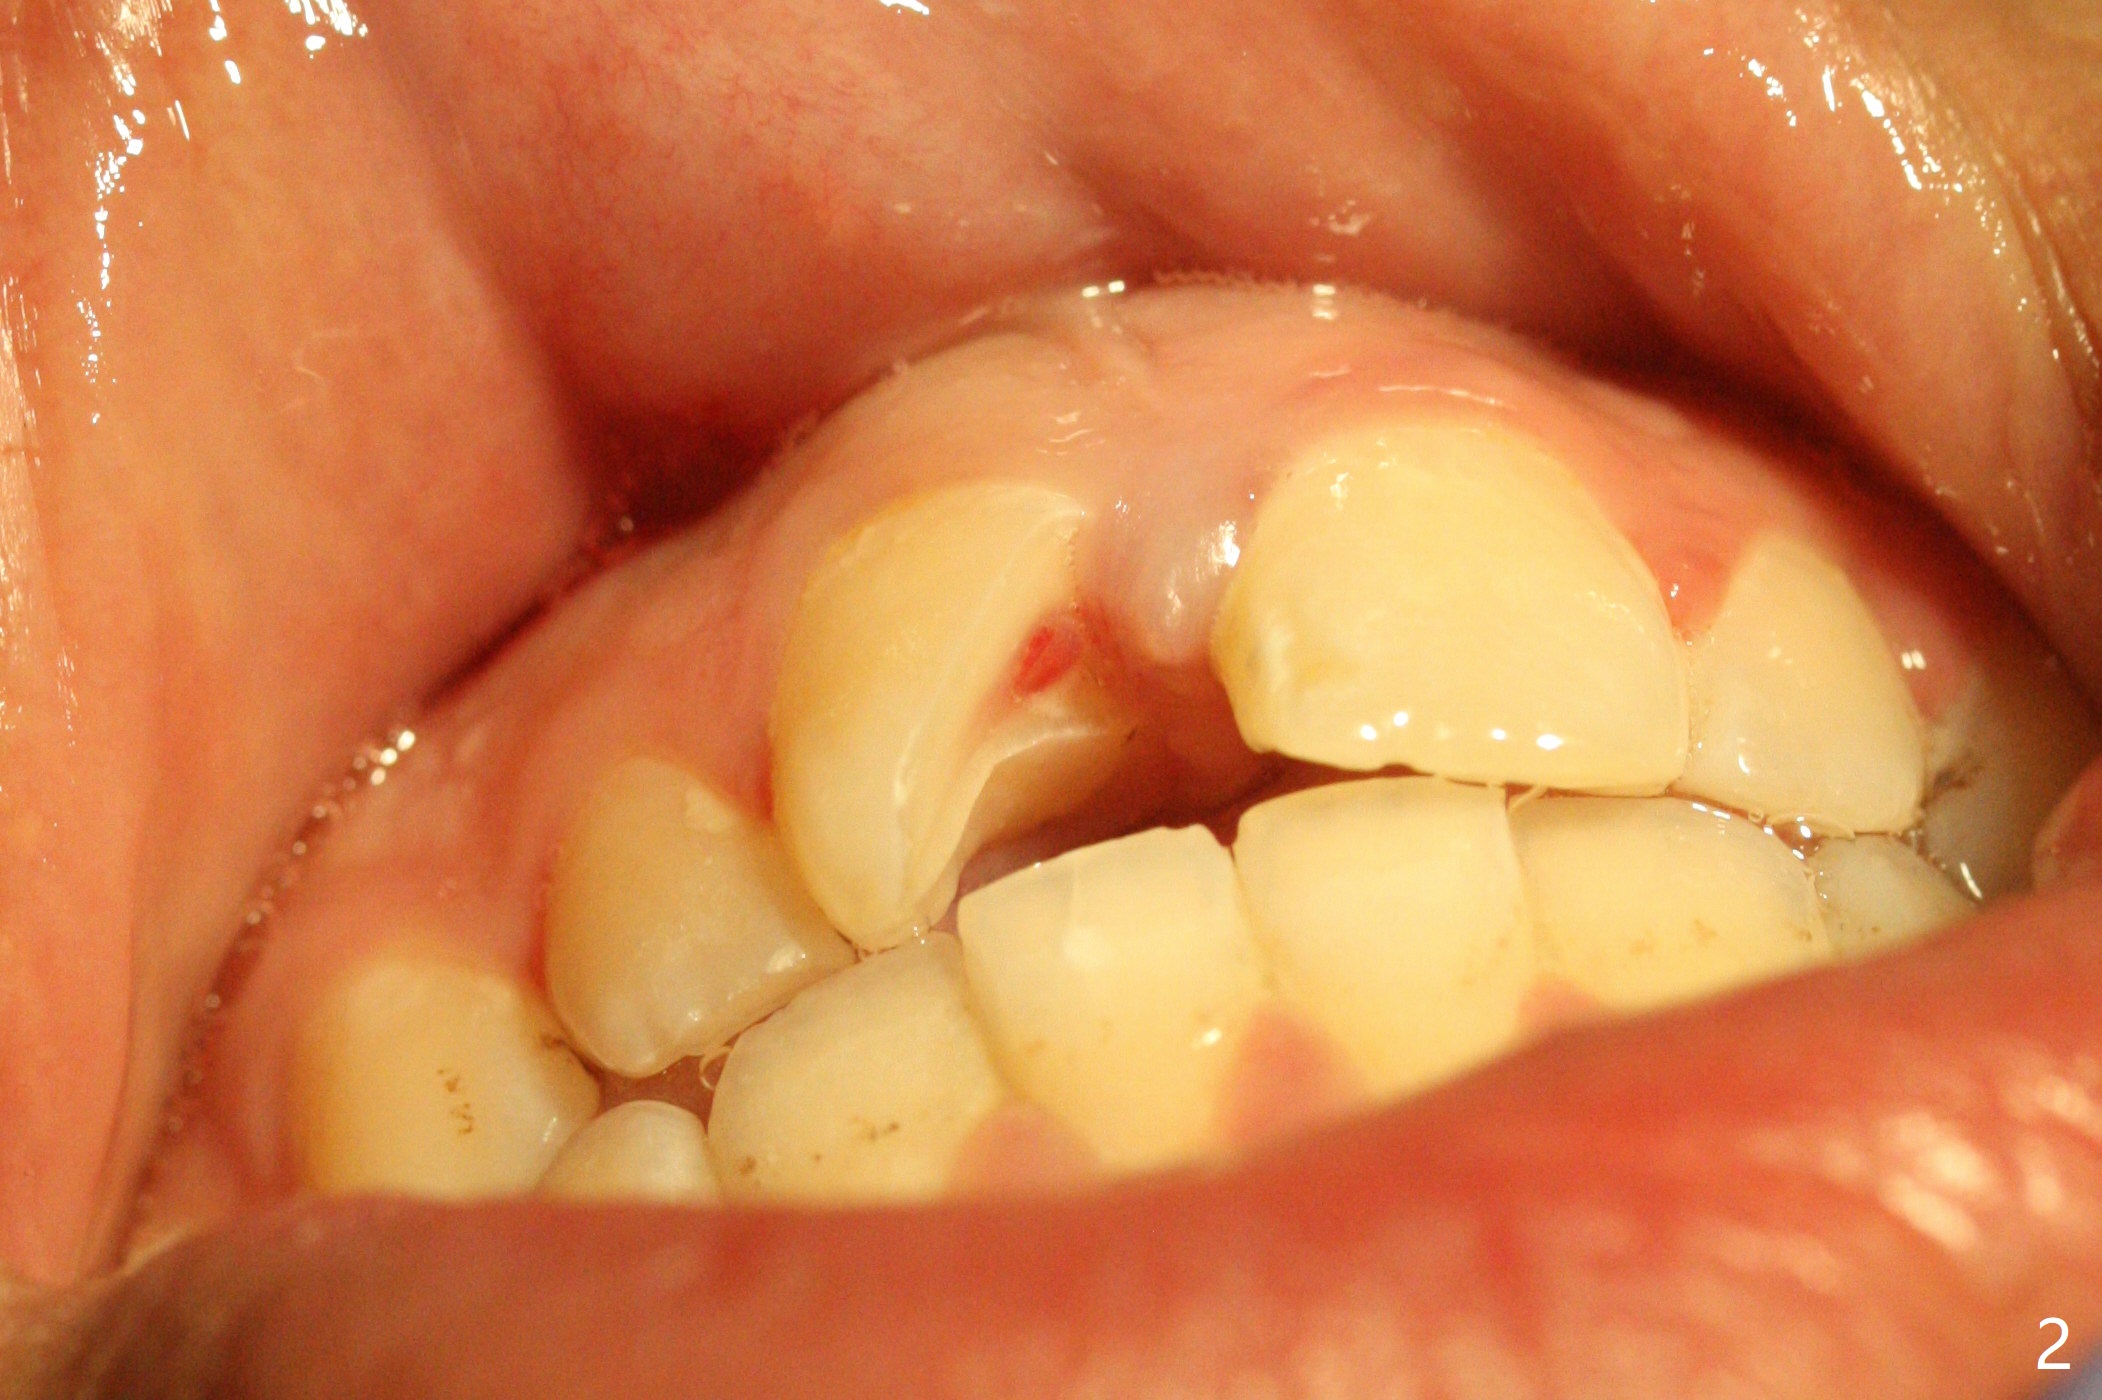

A 16-year-old man fractured the tooth #8 yesterday (Fig.1) with pulpal exposure (Fig.2) and slightly subgingival (Fig.3 <). With 2 gingival retraction cords, rubber dam and floss, the mesial margin is exposed (Fig.4). The mesial pulpal horn is increased slightly with a 330 bur with minimal pulpotomy. MTA is applied (Fig.5 <). A curette is placed over the MTA for hemostasis while it is setting. RelyX Ultimate Adhesive Resin Cement bonding is used to reattach the fracture fragment in place (Fig.6,7). Pulpal vitality will be monitored. A crown will be placed if the tooth discolors due to MTA and the pulp remains vital. Mineral trioxide aggregate (MTA), composed mainly of tricalcic silicate, tricalcic alluminate, bismuth oxide, is a particular endodontic cement. It is made of hydrophilic fine particles that harden in the presence of dampness or blood. The re-attached tooth remains asymptomatic 9 days postop (Fig.8) when he returns for prophy.

16岁男孩,昨天右上中切牙撞击电脑发生折裂(图一),近中牙髓角暴露(图二),裂缘稍微龈下(图三 <),使用两个牙龈牵拉线,橡皮障和牙线,近中折裂边缘暴露(图四)。你会如何处理?使用330钻头稍微扩大髓角开口,去除少量牙髓,填入微量MTA (图五<),希望形成新的牙本质,关闭开口,维持牙髓活性。出血控制后,应用树脂粘合剂将断片固定于原位(图五,六,七)。术后9天牙齿无症状(图八),病人回来洗牙。